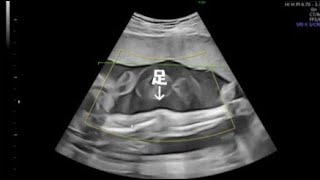

妊娠7か月【26週0日】足が長~い 4D エコー動画

ハリネズミ、時々モモンガと猫

2023.08.11 10:00

妊娠7か月【24週0日】4D エコー動画

2023.08.10 22:31